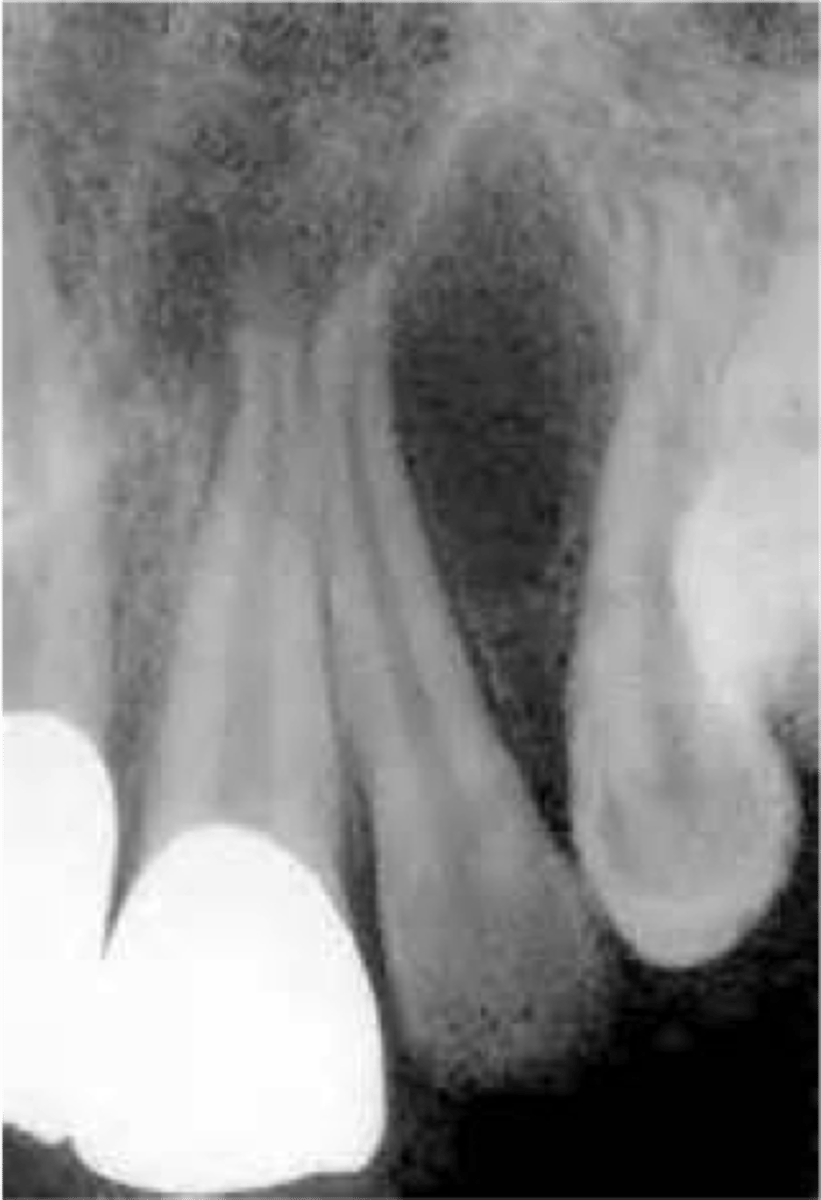

what is dentinogenesis imperfecta

a genetic condition characterized by blue translucent teeth, short roots, and no pulp

multiple radiolucencies = PA abscesses

what is dentin dysplasia and its 2 types

type 1 → most common; normal crown + short roots + no pulp; PA abscesses

type 2 → rare; normal crown + normal roots + thistle pulp; primary teeth have an amber crown appearance